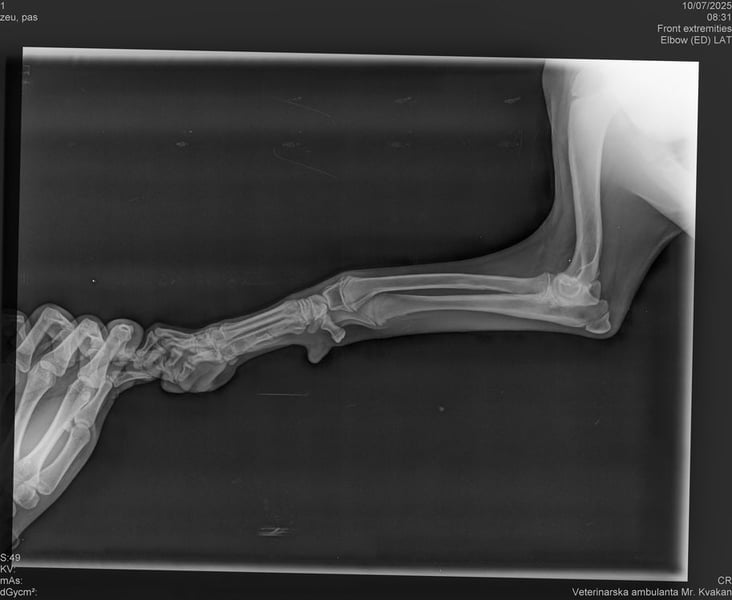

Bemerkungen: Unda humpelt ein wenig. Es sind Röntgenbilder vorhanden und darauf ist nichts ungewöhnliches zu erkennen. Momentan bekommt sie Schmerzmittel und die Angelegenheit wird Tierärztlich beobachtet

Die kleine Unda kam aus einer Romasiedlung. Wir konnten beobachten, dass sie ein wenig humpelt. Aus diesem Grunde durfte Unda im Tierheim einziehen. Sie wird nun tierärztlich überwacht. Die angefertigten Röntgenbilder lassen nichts ungewöhnliches an ihren Beinchen erkennen. Momentan bekommt Unda Schmerzmittel und die Angelegenheit wird weiterhin tierärztlich beobachtet